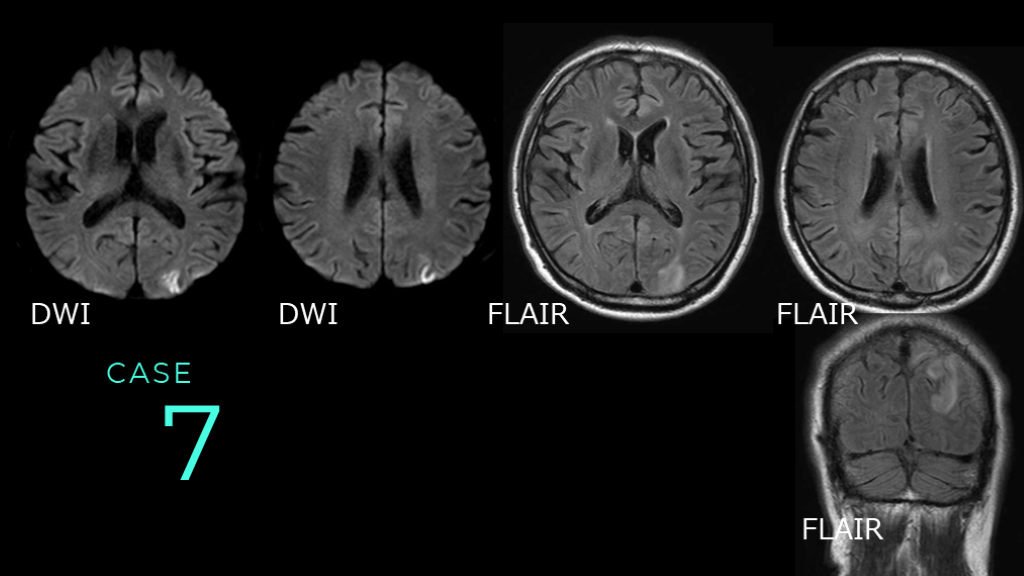

CASE 7 DWI DWI FLAIR FLAIR FLAIR

CASE 7 DWIでは左の後頭葉と頭頂葉皮質の高信号変化あり。 FLAIRではDWI病変の皮質を含む白質の淡い高信号変化を認める。 DWI DWI FLAIR FLAIR

CASE 7 コメント:脳炎症例。 DWI所見よりもFLAIR所見の方が広い。 ここまでの脳梗塞症例とは画像の違いがわかる。